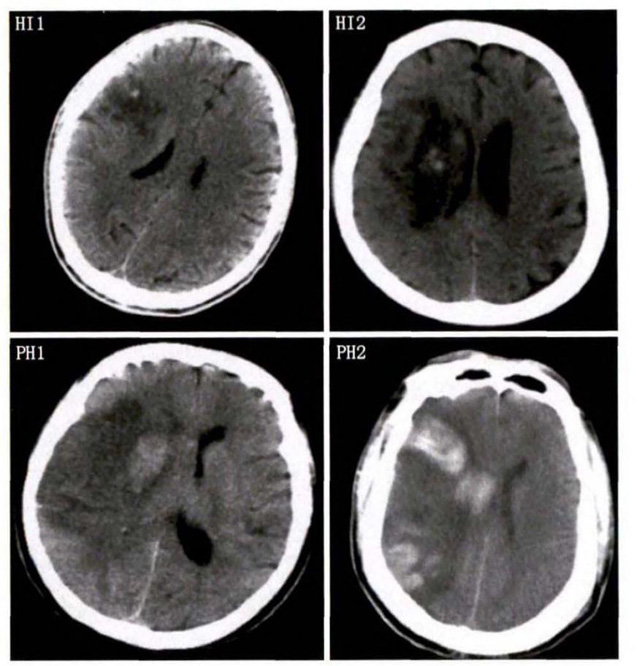

中、老年病患,有動脈粥樣硬化及高血壓病等腦卒中的危險(xiǎn)因素,發(fā)病結(jié)合神經(jīng)系統(tǒng)癥狀和體征,應(yīng)當(dāng)考慮急性腦梗死的可能。再經(jīng)腦CT/MRI發(fā)現(xiàn)梗死灶,或排除腦出血、炎癥性疾病等,診斷即可確定。腦梗死有時頗似小量腦出血的臨床表現(xiàn)。腦栓塞在任何年齡都可以有發(fā)病的風(fēng)險(xiǎn),可以在幾秒到幾分鐘達(dá)到頂峰。會有偏癱不能說話等局部神經(jīng)功能損壞。栓子來源很種,可能是冠心病、心肌梗塞、心內(nèi)膜炎等。合并心房纖顫,結(jié)合其他臟器官的支持診斷,CT跟磁共振都可以檢查確定栓塞位置數(shù)量還有是不是有伴發(fā)出血等問題。可以幫助診斷。

中老年有高血壓糖尿病發(fā)病病史,起病神經(jīng)功能缺損癥狀,臨床表現(xiàn)為腔隙綜合征,即可初步診斷本病。如果CT或磁共振證實(shí)有與神經(jīng)功能缺失一致的腦部腔隙病灶, 符合大腦半球或腦干深部的小穿通動脈病變,即可明確診斷。少數(shù)患者隱匿起病,無明顯臨床癥狀,在影像學(xué)檢查時發(fā)現(xiàn)。